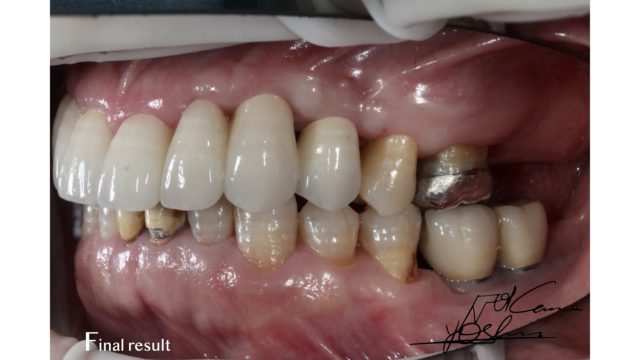

お口の右側、BEFORE写真です。

お口の右側、AFTER写真です。